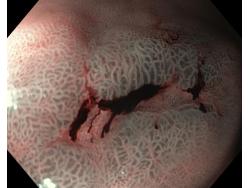

Celiakia